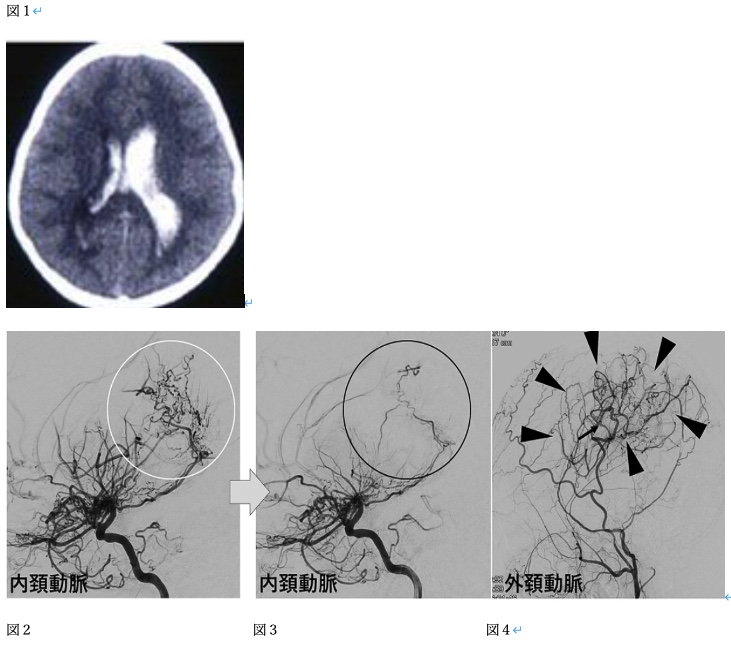

2022 B44 40歳女性。意識障害にて搬送された。その際の頭部CTを図1に示す。入院中に行った血管造影を図2(左内頚動脈側面像)に示す。この疾患に対して手術加療を行った。手術加療を行った三ヶ月後の血管造影を図3、4(左内頚動脈側面像、左外頸動脈側面像)に示す。 術後の病態に関連するもの2つを選べ。

Internal carotid-External carotid conversionが発生している, 出血リスクが低下している